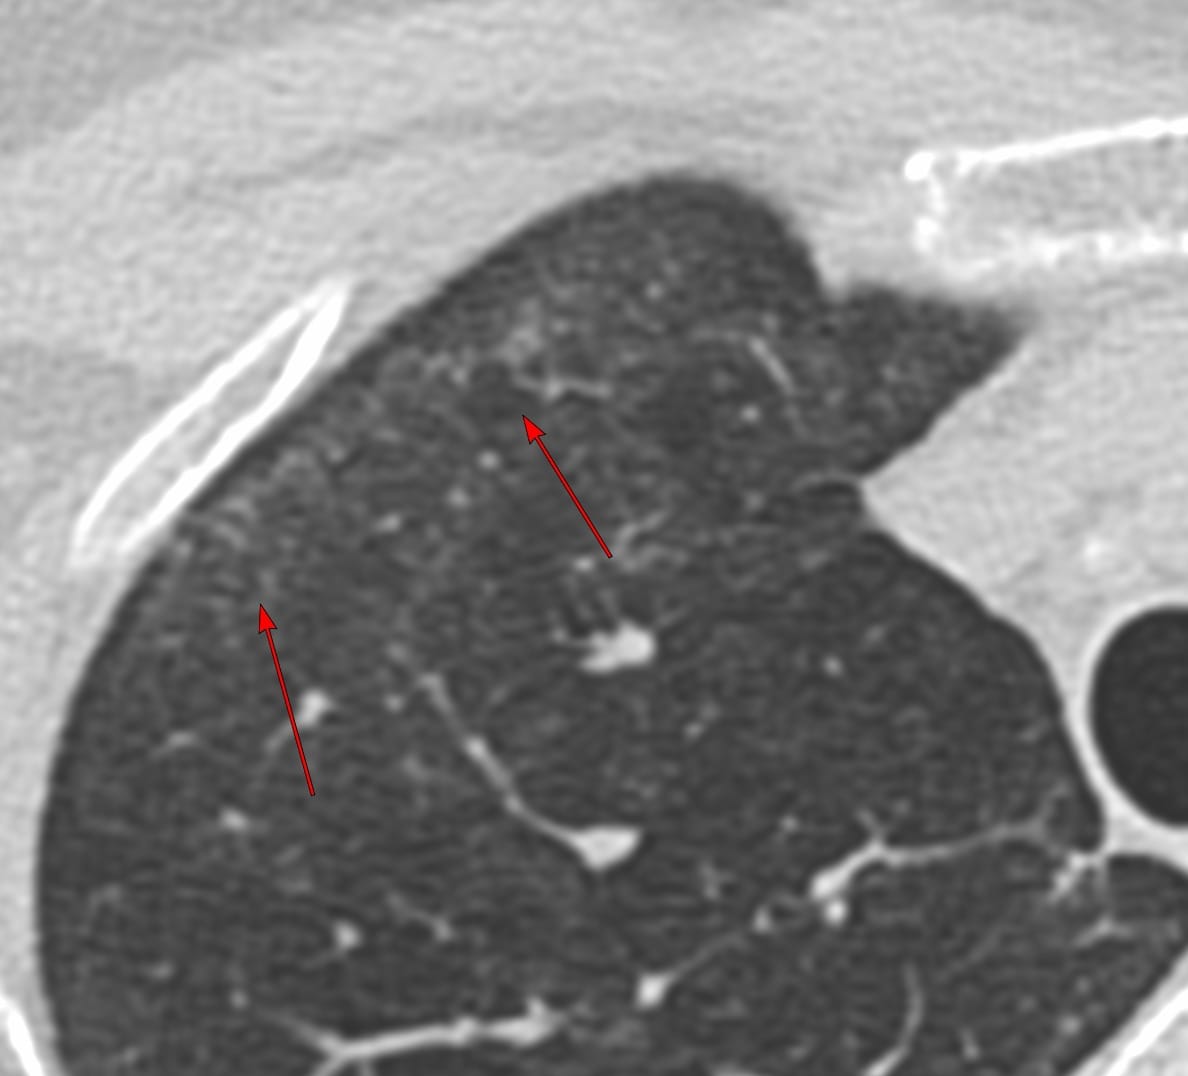

33-years old with scleroderma and scleroderma ILD with a fibrotic non-specific interstitial pneumonia (NSIP) pattern.

The upper lobes show interstitial lesions, typically considered to be part of the NSIP pattern.

A recent Japanese paper introduces the concept of FANO - faint amorphous nodular opacities - first described with asbestosis, which are seen typically in the anterolateral non-dependent upper lobes and most commonly associated with an NSIP pattern and are known to progress and likely represent early-stage interstitial disease.

This brings to focus the likelihood that the early stage scleroderma ILD cases I have shown earlier have also likely been FANO lesions.